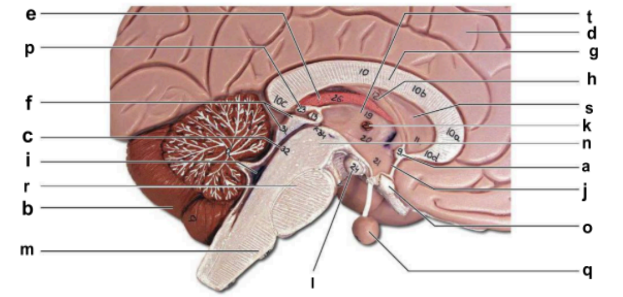

Identify the structure labeled “a” in the image.

anterior commissure

Identify the structure labeled “b” in the image.

cerebellum

Identify the structure labeled “c” in the image.

cerebral aqueduct

Identify the structure labeled “d” in the image.

cerebral hemisphere

Identify the structure labeled “e” in the image.

choroid plexus

Identify the structure labeled “f” in the image.

corpora quadrigemina

Identify the structure labeled “g” in the image.

corpos callosum

Identify the structure labeled “h” in the image.

fornix

Identify the structure labeled “i” in the image.

fourth ventricle

Identify the structure labeled “j” in the image.

hypothalamus

Identify the structure labeled “k” in the image.

interthalamic adhesion

Identify the structure labeled “l” in the image.

mammilary body

Identify the structure labeled “m” in the image.

medulla oblongata

Identify the structure labeled “n” in the image.

midbrain

Identify the structure labeled “o” in the image.

optic chiasma

Identify the structure labeled “p” in the image.

pineal gland

Identify the structure labeled “q” in the image.

pituitary gland

Identify the structure labeled “r” in the image.

pons

Identify the structure labeled “s” in the image.

septum pellucidum

Identify the structure labeled “t” in the image.

thalamus